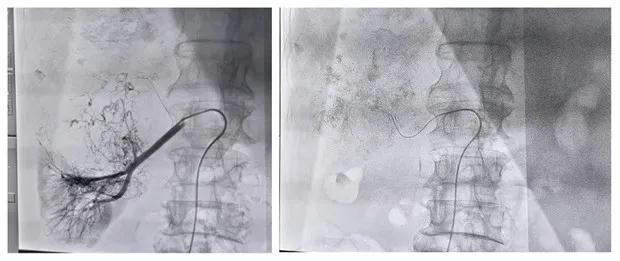

患者男性,69岁,因“右胁部胀痛伴乏力3月,发现肝占位2天”。入院行MRI检查提示:右肾癌并出血,肝内及腹膜后淋巴结多发转移。与彩超室韩娟娟主治医师配合行彩超引导下肝脏肿瘤穿刺术,取病理示:查见低分化腺癌,倾向于透明细胞型。

明确诊断后,经科室讨论考虑,患者为肿瘤晚期,失去外科手术机会,经肝动脉及肾动脉栓塞化疗是目前治疗不能手术切除肿瘤的最好治疗方法。经与患方充分沟通后,给予行肝动脉及右肾动脉栓塞化疗术,手术顺利,术后患者恢复良好。

经动脉栓塞是阻断肿瘤的供血动脉,切断肿瘤细胞的营养供应,达到饿死肿瘤细胞的目的;同时给予肿瘤供血动脉灌注化疗,化疗药物浓度高,是常规静脉化疗药物浓度的1000倍,可有效杀死肿瘤细胞。